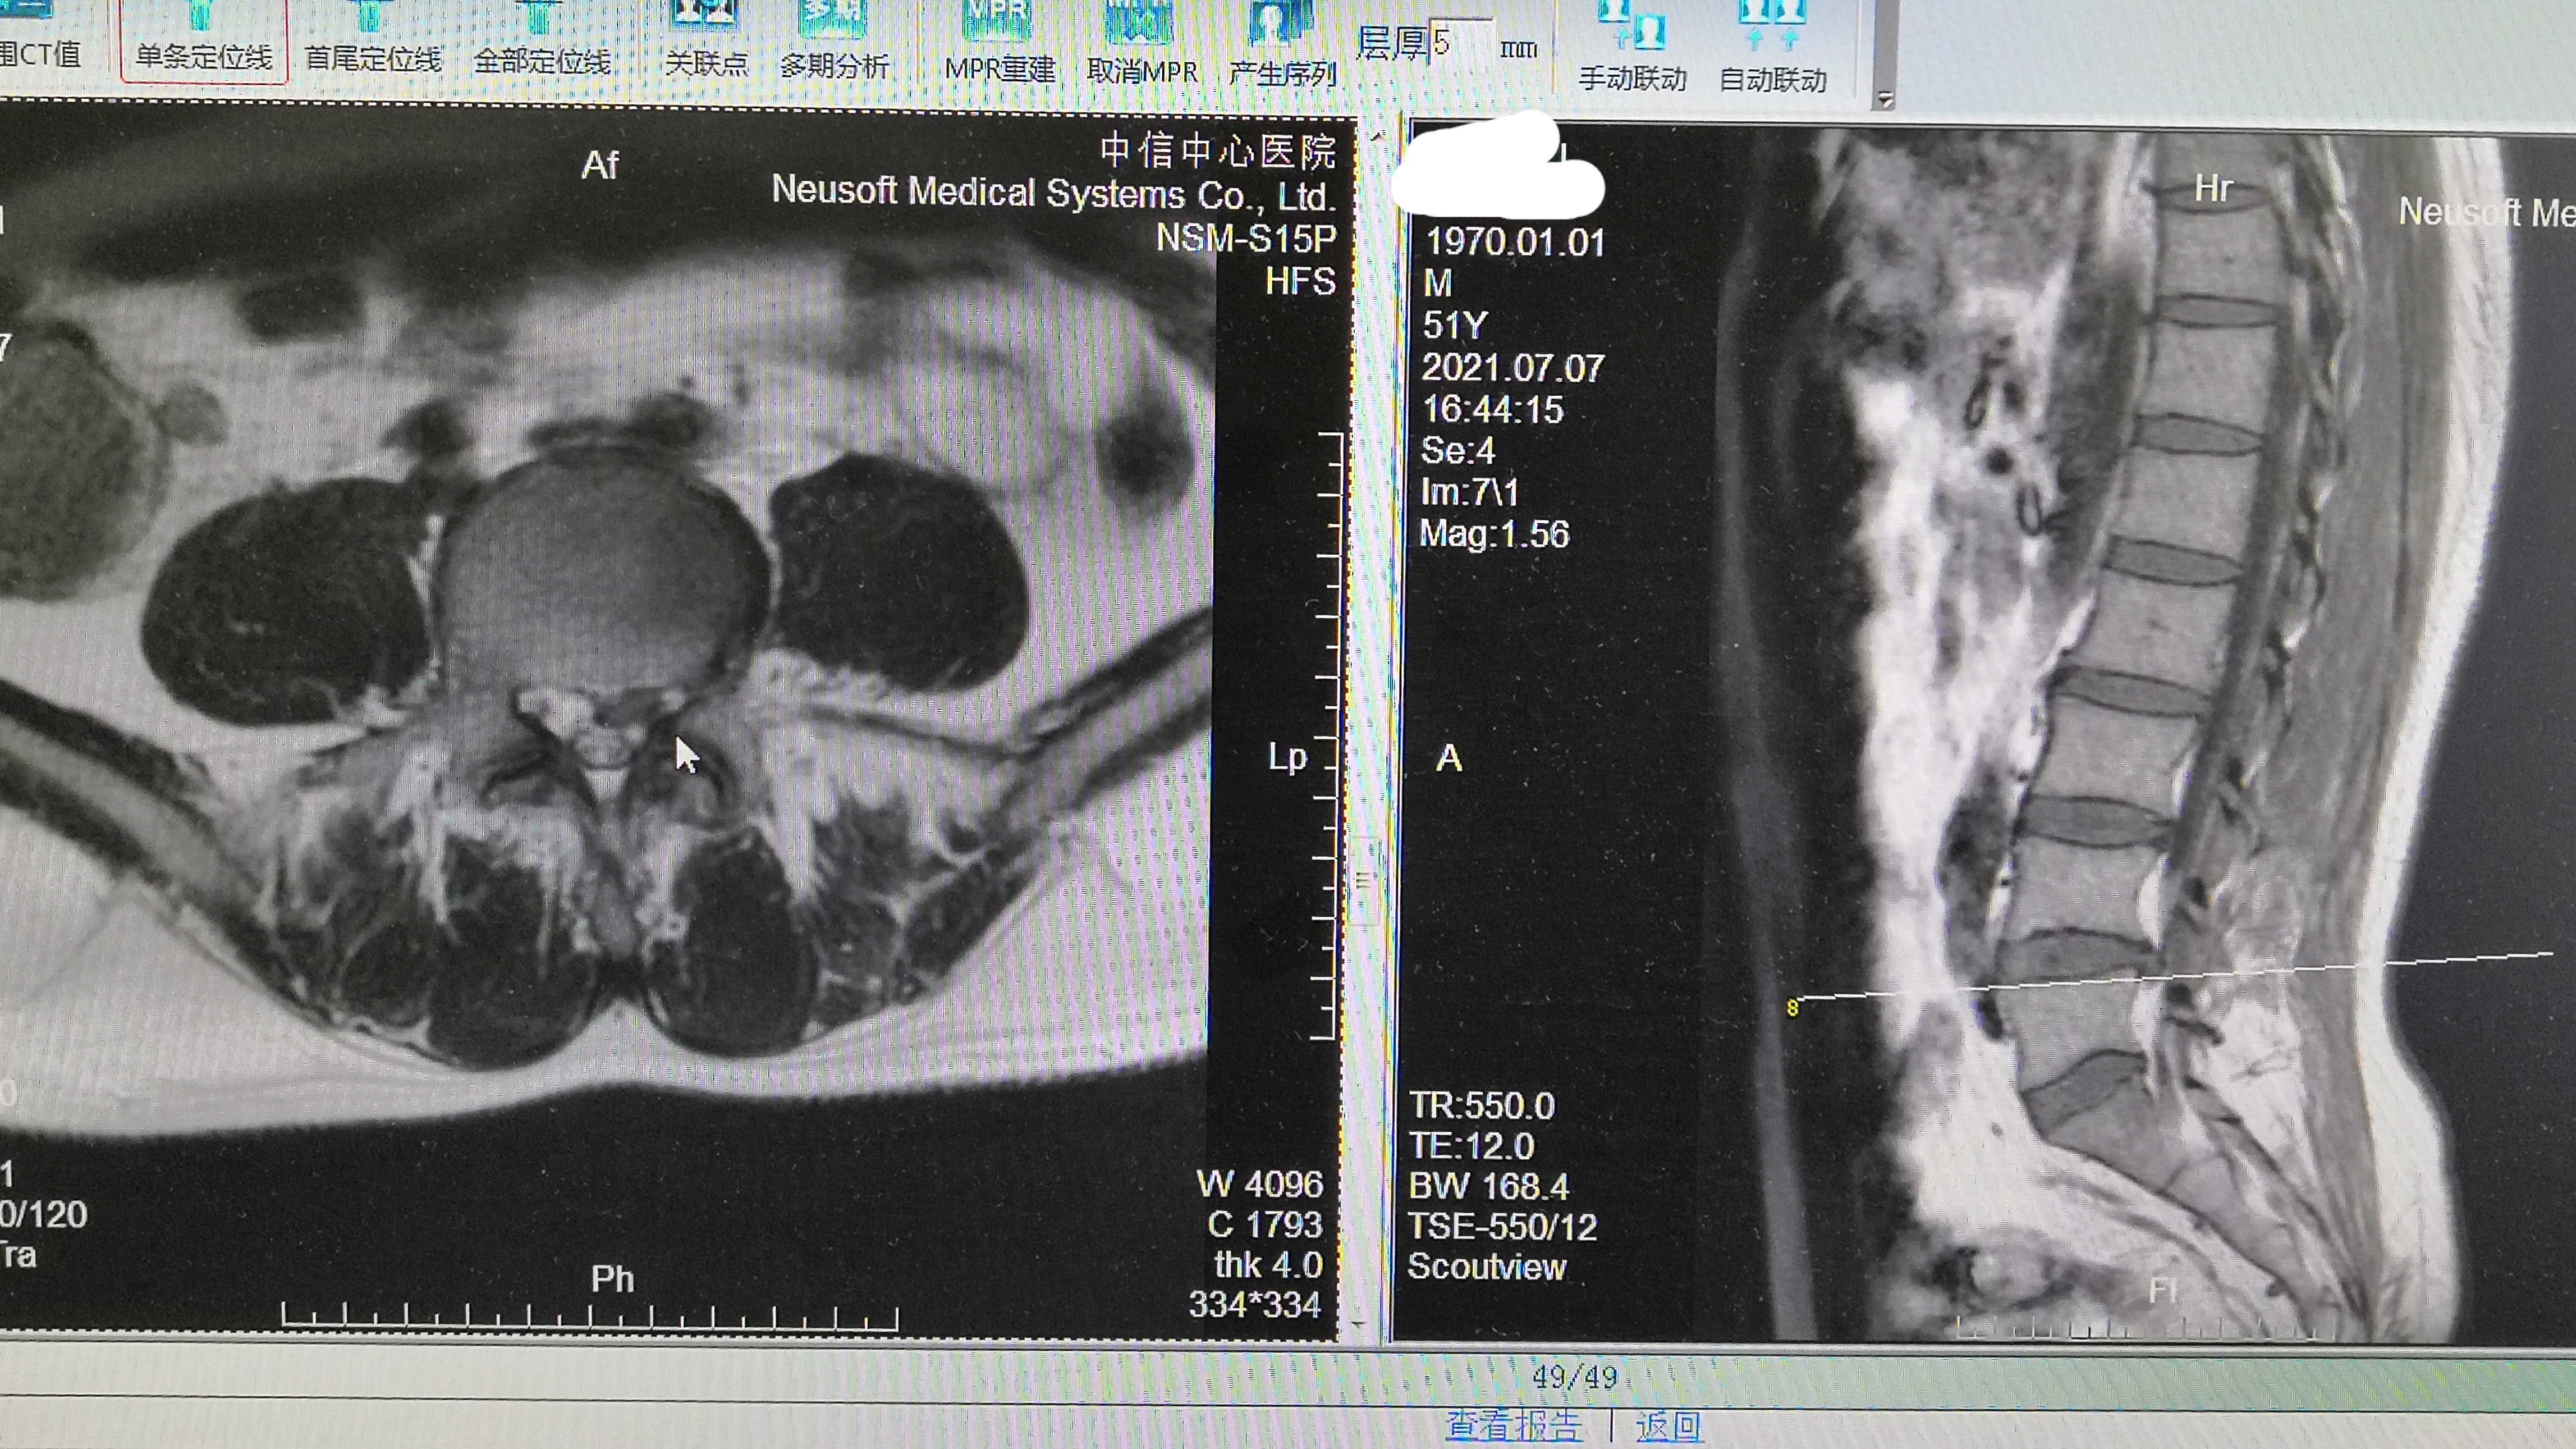

影像学检查表现:腰椎核磁共振检查

腰4-5椎间盘偏左后突出

硬膜囊以及神经根受压

腰椎核磁提示:腰4-5椎间盘左后突出